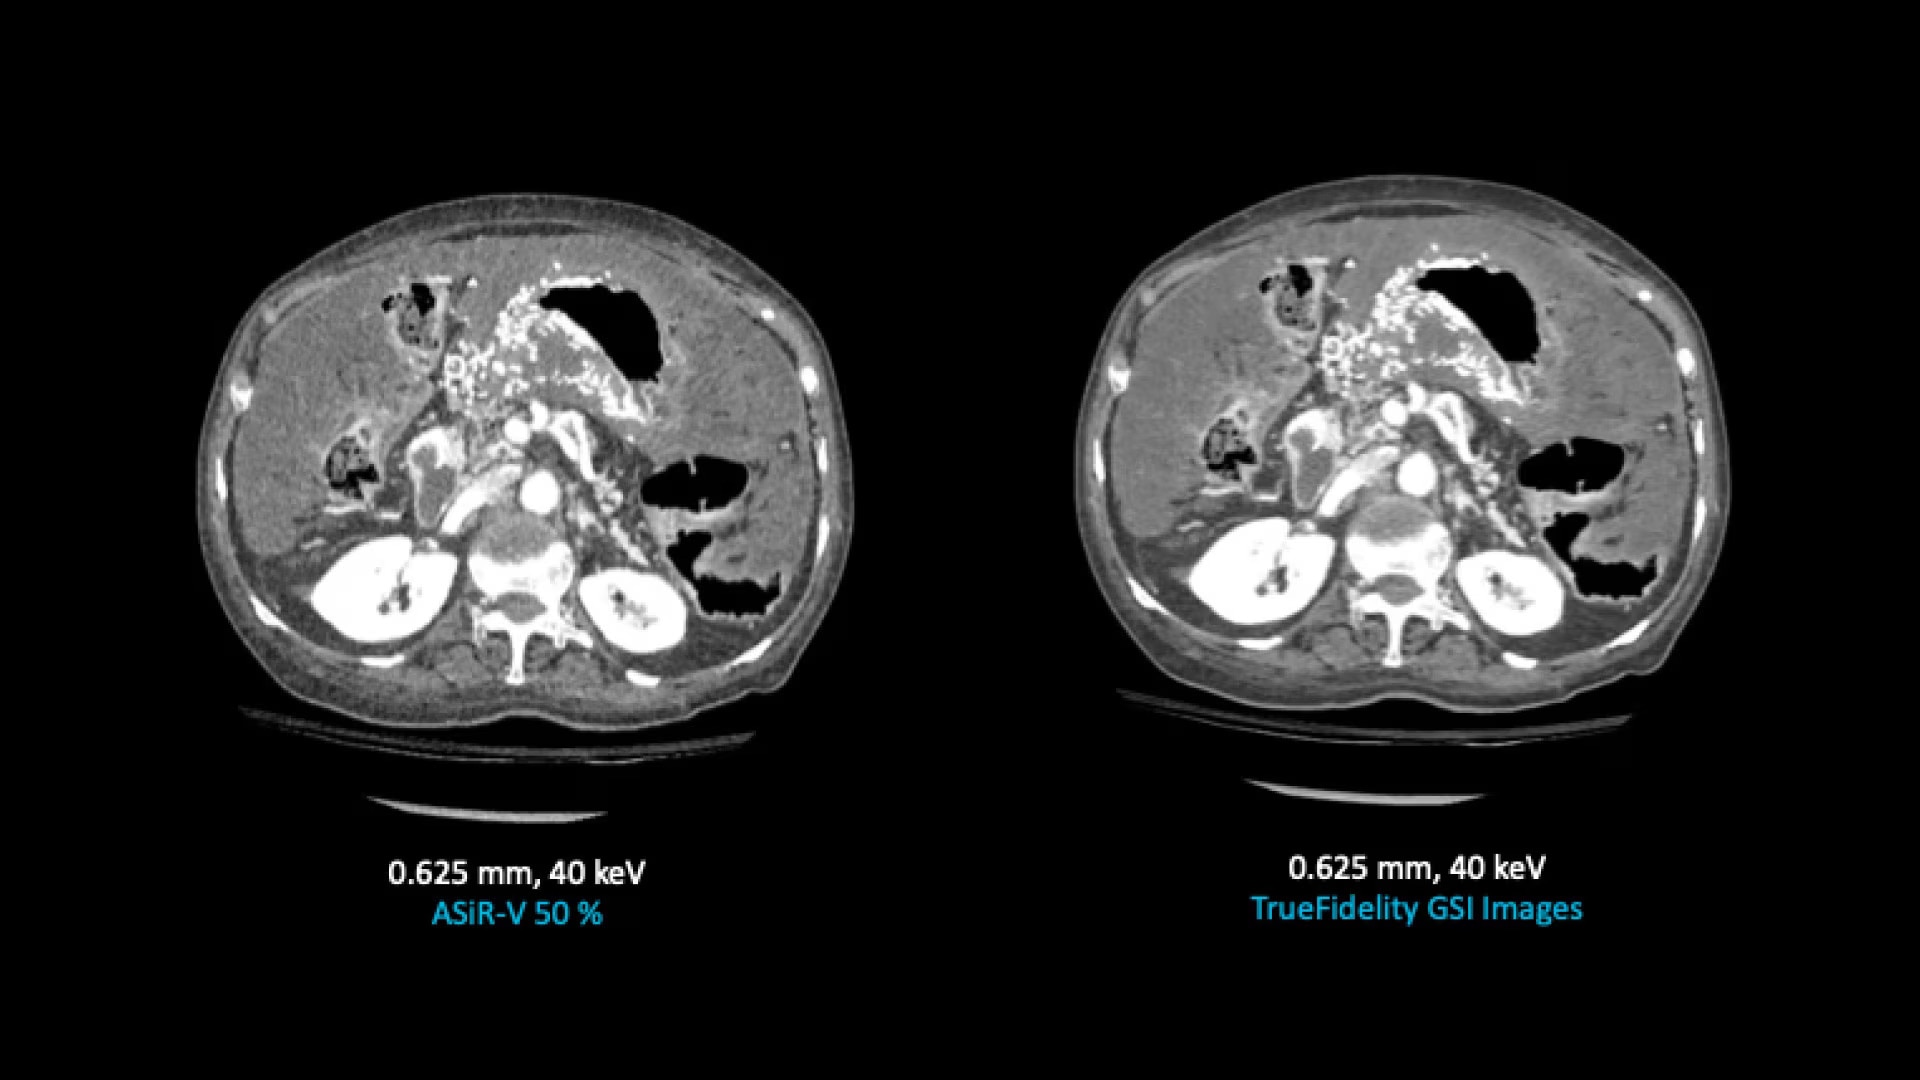

TrueFidelity for GSI now brings the potential to substantially reduce the image noise in all spectral image types

From virtual monochromatic images to material image pairs and virtual non-contrast images, with and without metal artifact reduction. Specifically, reducing the image noise inherent with low keV images resolves one of the traditional technical challenges in adopting more dual-energy protocols across the full patient population.